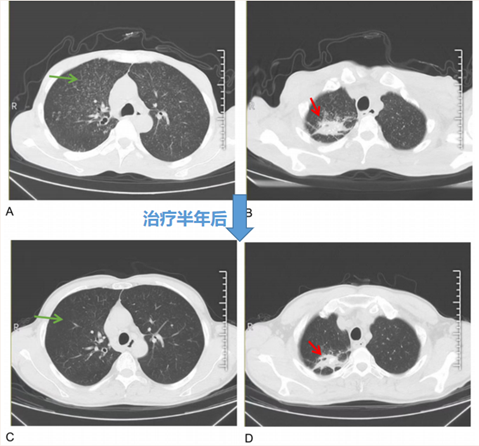

治疗半年后,IgG4(1.11 g/L)、肾功能(血肌酐93.6μmol/L)、尿TP/CR (214mg/g)、血清轻链κ/λ(154.35/39.68)及血三系、电解质等化验指标均明显好转;胸部CT提示双肺弥漫性粟粒样改变(A、C 中绿色箭头)几乎完全吸收,右肺上叶多形性病变得到控制(B、D 中红色箭头)。颈部B超提示淋巴结缩小。